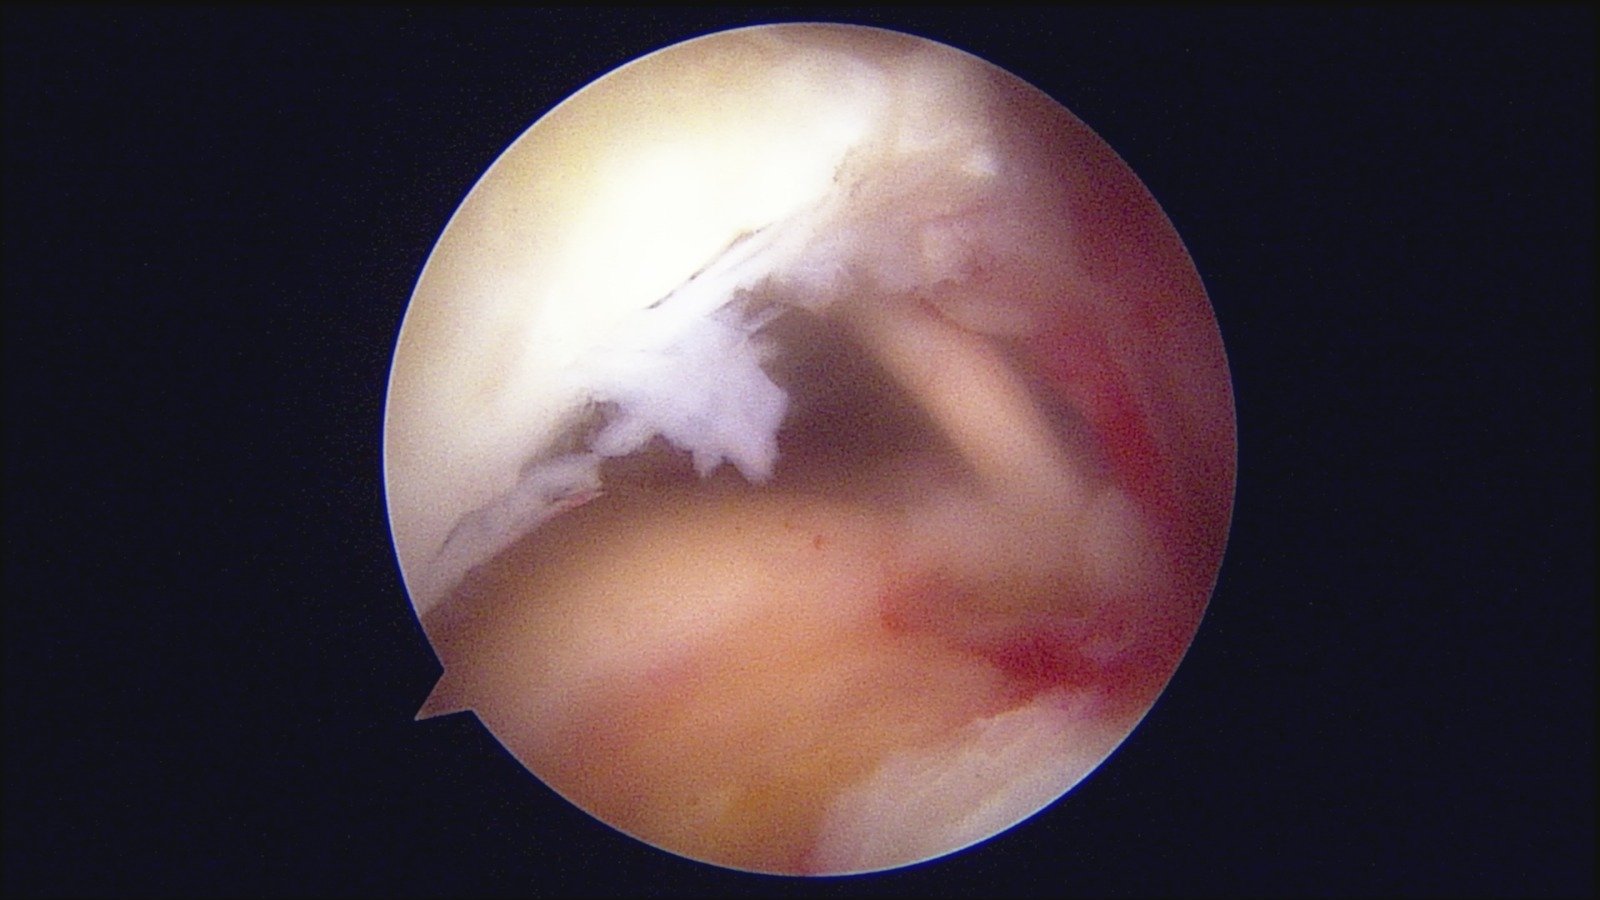

GalleryShoulder rotator cuff repair Meniscus root repair Meniscus repair Bankart repair for recurrent shoulder dislocation ACL reconstruction Machines Instruments